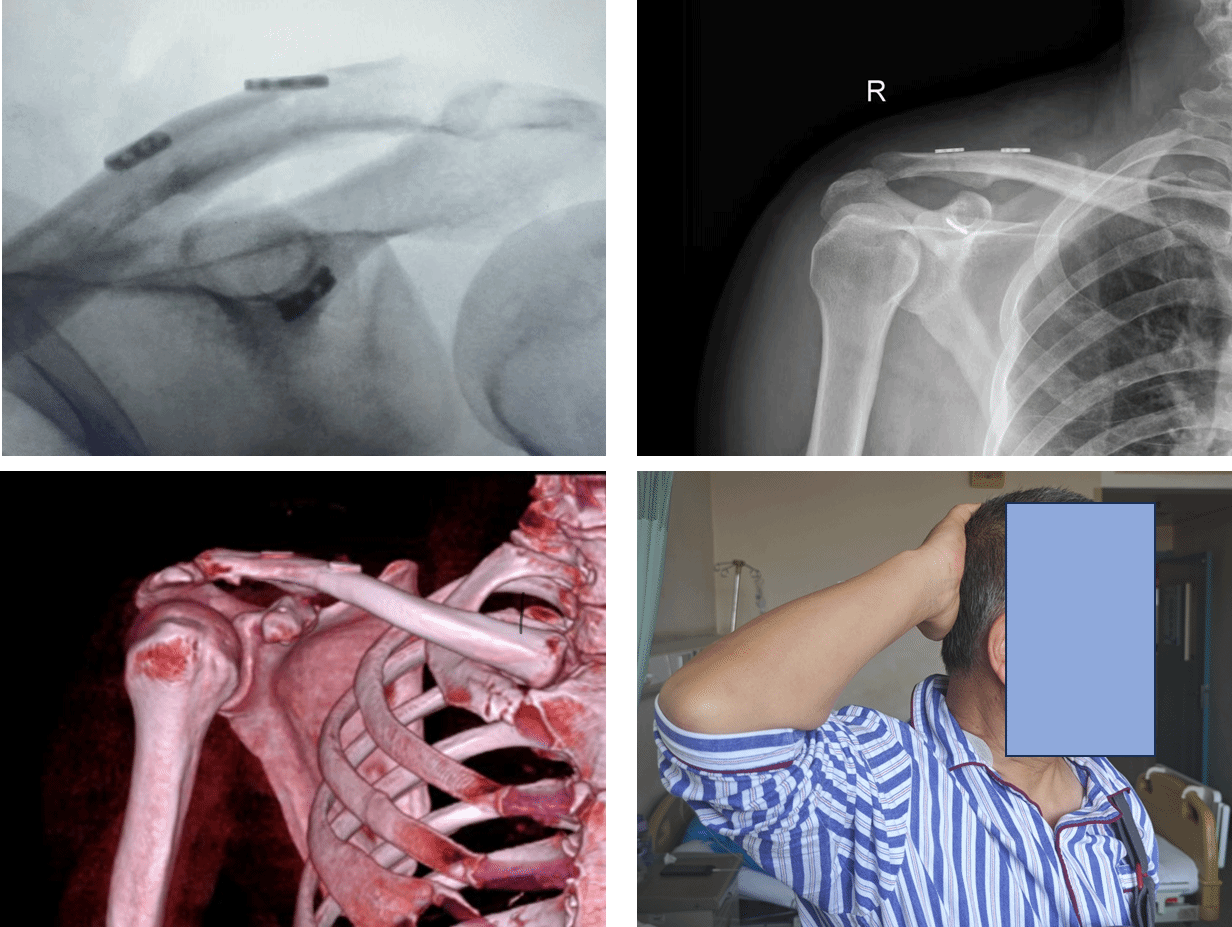

术中,根据完善的术前设计,倪建龙主刀,吕雷锋博士辅助,成功为患者王先生完成了陈旧性肩锁关节脱位的创新手术。倪建龙谈到,此次手术中,采用微创技术避免了肌肉剥离,患者术中出血不足50ml,有助于患者恢复;移植的肌腱在六周后会转化成韧带组织,发挥永久稳定作用;患者无需二次手术取出植入物,达到了永久治愈的治疗效果。

“‘三袢V形动力性重建术’尤其适合劳动者、运动员等高需求患者。”时志斌主任介绍,“三袢V形动力性重建术”是将微创切口、弹性固定与生物学重建三者融合,就像是给脱位的关节进行饱和式救援,袢钢板系统提供即时稳定,而自体肌腱会逐渐长成新韧带,这是永久性生物重建。V形袢板分散应力,肌腱缠绕弥补了纯金属固定的“无生命”缺陷——这是肩锁关节脱位治疗从“机械修复”迈向“生物再生”的关键一步。

近日,我院骨科中心运动医学病区在时志斌主任的指导下,由倪建龙副主任医师团队成功为患者王先生完成了陈旧性肩锁关节脱位的创新手术,术中仅通过2个微创切口,采用全镜下“袢钢板V形系统+自体肌腱移植”技术,重建了肩关节稳定性。术后24小时,王先生的疼痛评分从8分降至2分;术后48小时,在康复治疗师指导下,王先生可完成外展及摸头训练,已能抬手摸头。“感觉肩膀终于活过来了”。王先生激动地说。